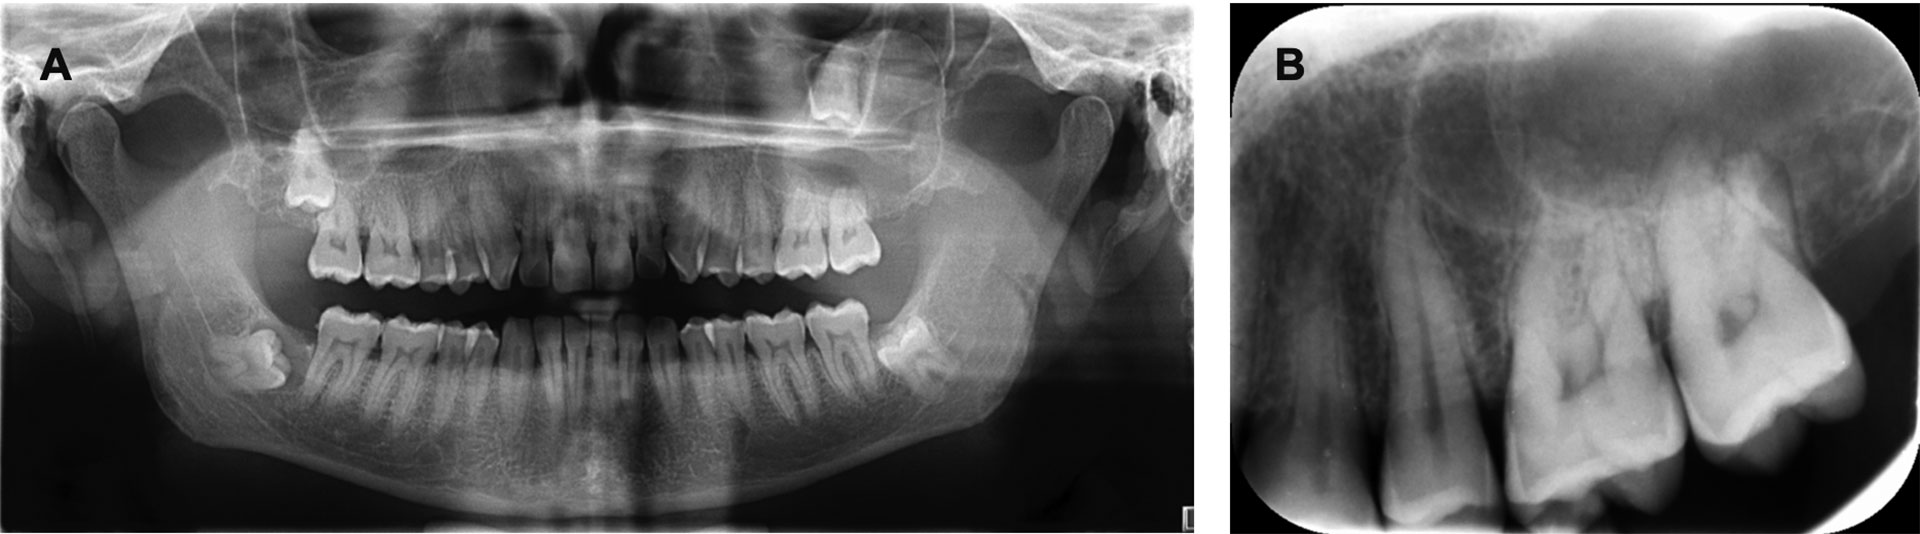

Panoramarøntgen og CBCT viste retinerte visdomstenner 18, 28, 38 og 48 (figur 1). Det ble påvist en stor cystisk prosess som fylte ut deler av den venstre delen av kjevekammen i overkjeven, samt en betydelig del av venstre maxillarsinus. Prosessen hadde en tynn bengrense mot den ellers luftfylte øvre delen av bihulen. Det forelå fortynning og ekspansjon av både lateral og posterior sinusvegg. Tann 28 var displassert kranialt i retning orbitagulvet (figur 2). Marginalavgrensningen av prosessen var noe utvisket, og det forelå lett resorpsjon av apices på tann 26 og 27 (figur 1 B). Radiologisk tentativ diagnose var en cystisk prosess, mest forenlig med enten en keratocyste eller follikulærcyste i venstre del av maxilla og maxillarsinus.

Figur 1. Preoperative panorama- og periapikalrøntgen av pasienten før kirurgisk ekstirpasjon av tenner 27, 28 samt cystektomi. A: Preoperativt panorama. Retinerte visdomstenner og tann 28 displassert mot orbita i en cystisk prosess. B: Intraoralt bilde av regio 24-28 som viser cystens anteriore og kaudale begrensing.